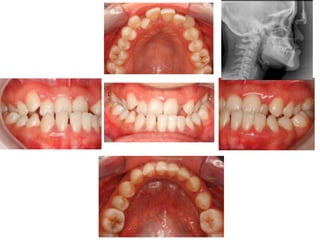

Case 1

23 years old, F

Engineering student, well motivated

Long face

Concave facial profile

Facial asymmetry

Midline deviation

•Deviated midline

•Anterior and posterior

crossbite

•Naturally compensated

dentition